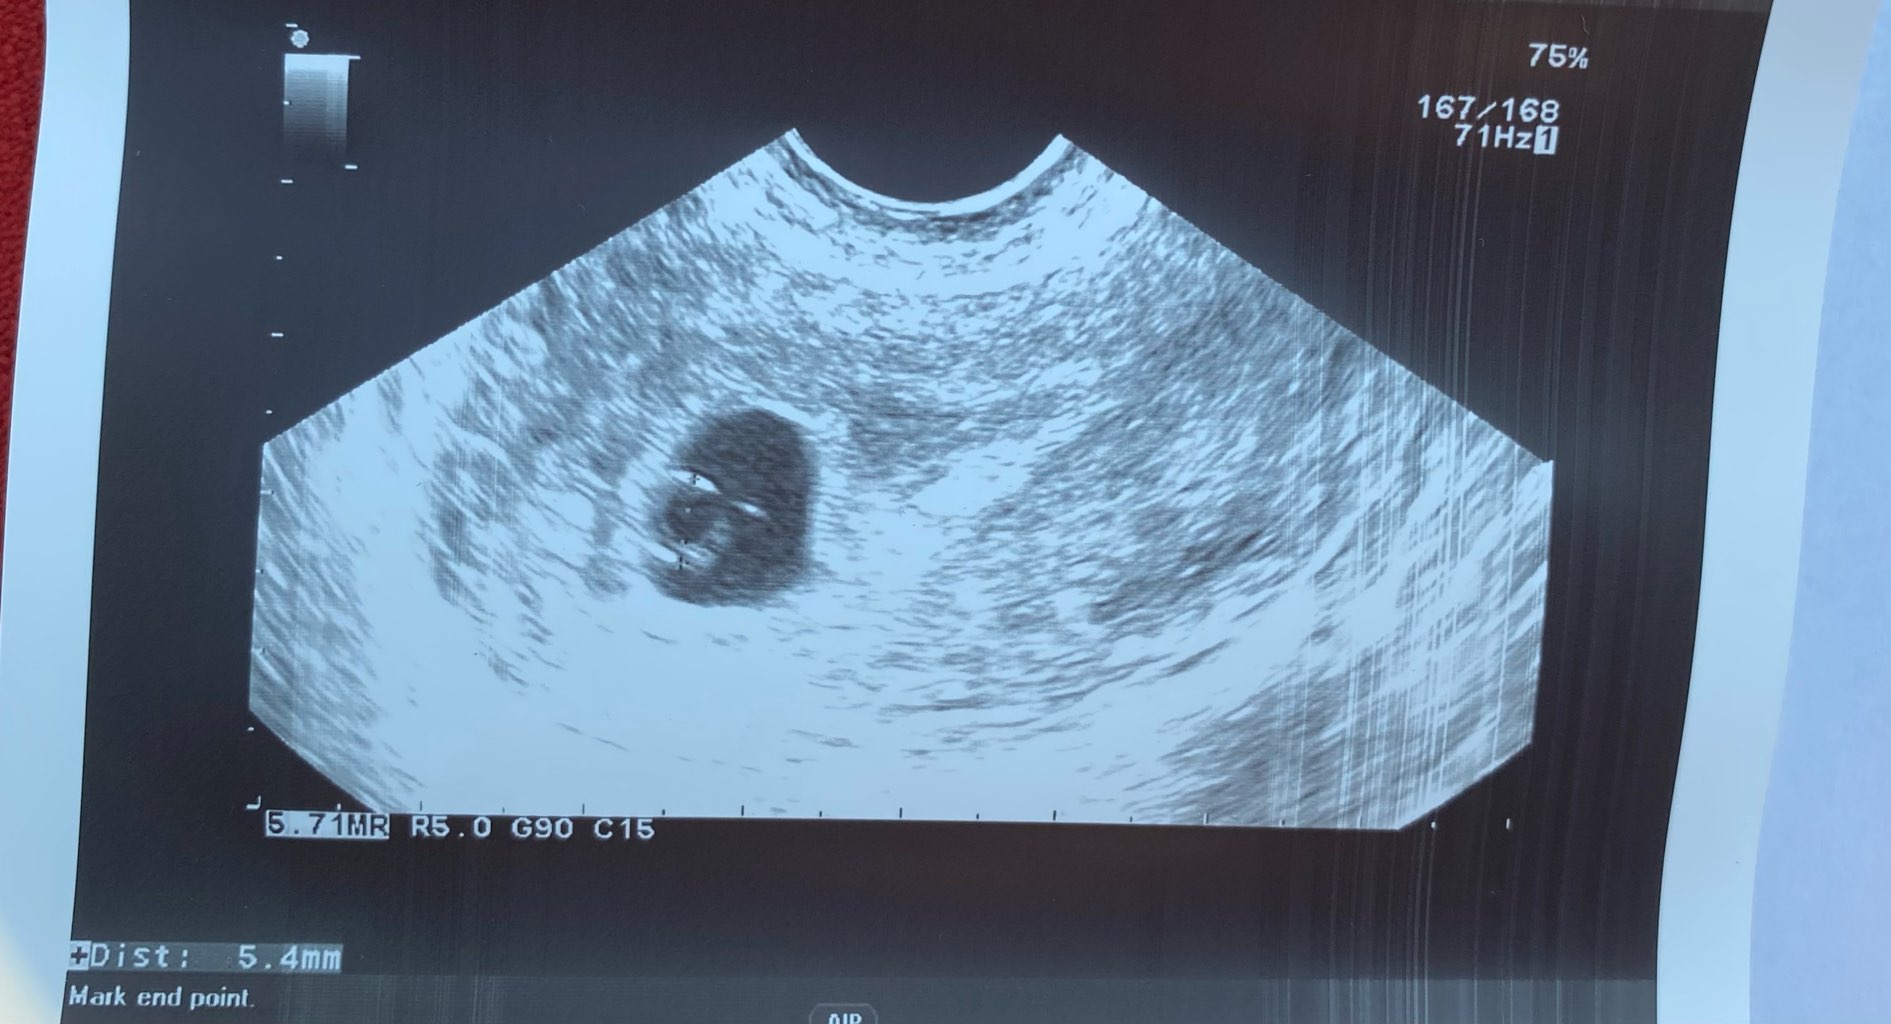

Jestem już po wizycie. Niestety echa zarodka nadal nie udało się wychwycić. Od poprzedniej wizyty 14.07 Pojawił się malutki zarodek 2,5 mm i mam pojawić się za 10 dni. Lekarz powiedział mi, ze mam się nie nastawiać ani za ani przeciw. Chyba, patrząc na Wasze historie, pójdę jeszcze do jakiegoś prywatnego z lepszym sprzętem usg, bo ten wydaje się nie być najwyższej jakości :)

Nie nastawiam się na najgorsze, bo podobno ciąża jest młodsza niż wychodzi z OM….

Wg OM wychodzi mi 7+0, zarodek odpowiada 5+5

• IMG_5102.jpg

IMG_5102.jpg

189,6 KB · Wyświetleń: 75